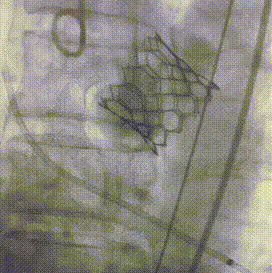

手术过程:

4、选用26mm SAPIEN 3瓣膜(减1cc容量),降主动脉处瓣膜组装后,顺利通过主动脉瓣,精确定位人工瓣膜,临时起捕器180bmp血压下降到50mmH以下,球囊扩张释放瓣膜。

6、瓣膜植入且撤出导丝后,造影超声结果均显示瓣膜工作良好,经胸超声检测少量瓣周漏,无传导阻滞,手术效果符合团队预期。